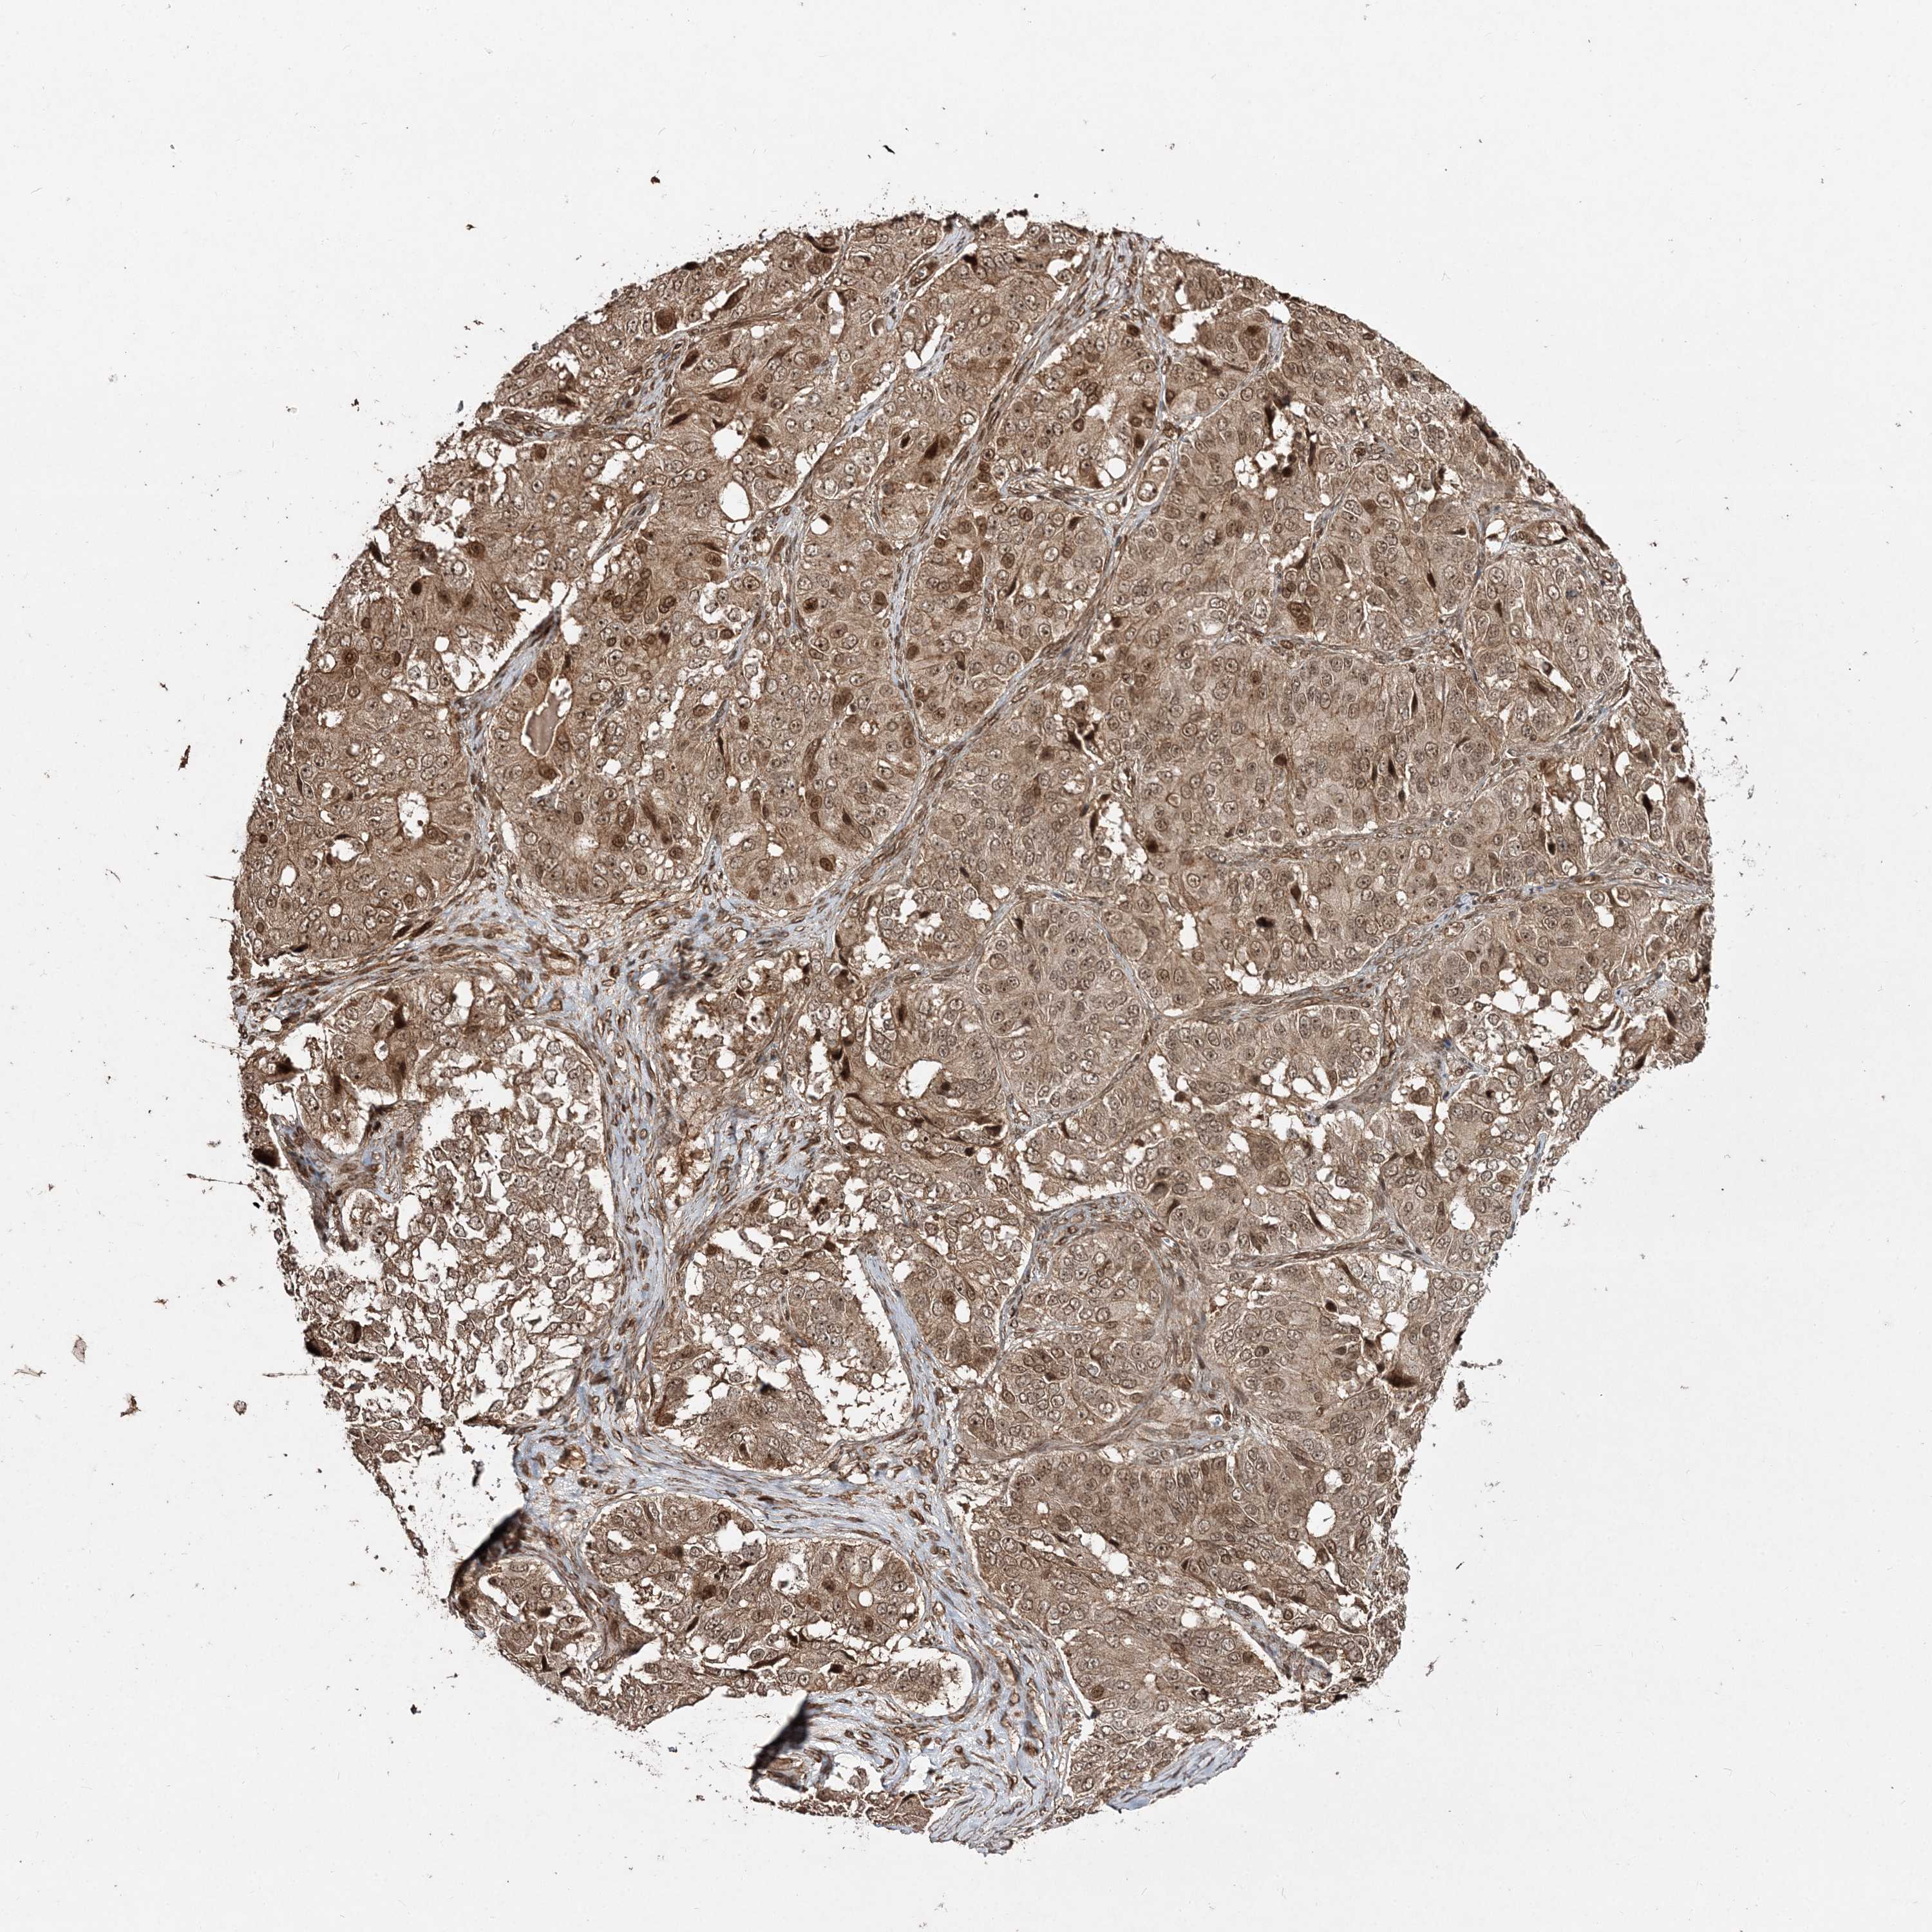

OVARIAN CANCER - Protein expressioni

A mouse-over function shows sample information and annotation data. Click on an image to view it in a full screen mode. Samples can be filtered based on level of antibody staining by selecting one or several of the following categories: high, medium, low and not detected. The assay and annotation is described here.

Note that samples used for immunohistochemistry by the Human Protein Atlas do not correspond to samples in the TCGA dataset.

Antibody stainingi

Antibody staining in the annotated cell types in the current human tissue is reported as not detected, low, medium, or high, based on conventional immunohistochemistry profiling in selected tissues. This score is based on the combination of the staining intensity and fraction of stained cells.

Each image is clickable and will lead to virtual microscopy that enables deeper exploration of all samples and also displays staining intensity scores, fraction scores and subcellular localization as well as patient and tissue information for each sample.

Antibody HPA035048

Antibody HPA035049

Cystadenocarcinoma, serous, NOS